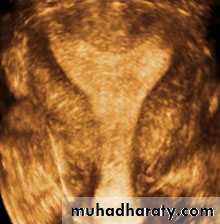

Bicornuate Bicollis Uterus• Congenital anomalies of uterus

• Didelphic uterus with Left sided hematometra• Congenital anomalies of uterus